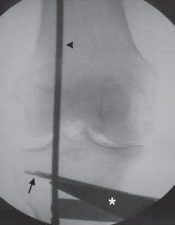

4. Using fluoroscopy, the alignment rod is placed at the center of the femoral head (

TECH FIG 3A

) and then at the center of the ankle joint (

TECH FIG 3B

).

D E TECH FIG 3•A.

Fluoroscopic image of alignment rod through femoral head.

B.

Fluoroscopic image of the alignment rod in the center of the ankle.

C.

The subsequent location of the alignment rod in the knee. This initial mechanical axis must be corrected. It should match with the preoperative planning.

D.

Initial guide pin from medial to lateral and parallel to the joint line. The pin is placed approximately 1 cm distal to the joint line.

E.

Osteotomy guide pin assembly over the initial guide pin. The angle of the guide pin assembly is changed so that the guide pins are just superior to the tibial tubercle. Two pins are drilled from medial to lateral along the osteotomy line to intersect the initial guide pin 1 cm from the lateral cortex.

F.

Fluoroscopic image verifying the two guide pins placed from medial to lateral using the osteotomy guide pin assembly. Note how in this view, which is parallel to the joint surface, the two pins are superimposed on one another, thus verifying that they, too, are parallel to the joint surface.

White arrow,

guide pin assembly;

black arrow,

osteotomy guide pins;

black arrowhead,

initial guide pin.